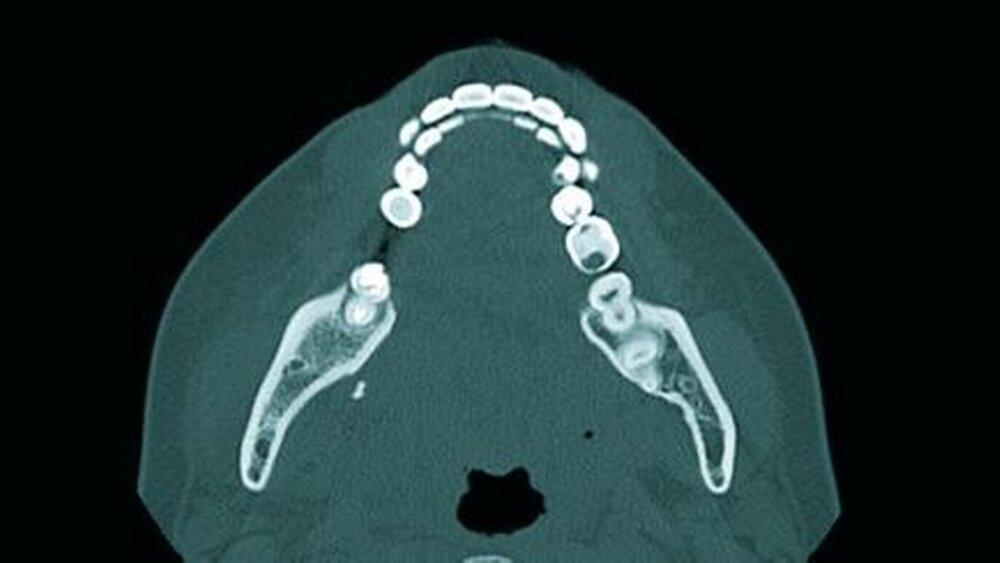

In einem zweiten Patientenfall wurde uns eine Patientin mit einem ähnlichen Kasus in die Universitätsklinik Jena überwiesen. Nach einem Versuch der operativen Weisheitszahnentfernung des Zahnes 48 alio loco (Abbildung 6), wurde ein Wurzelrest in den Mundboden versprengt. Der Fall verdeutlicht die Wichtigkeit der dritten Dimension bei der Beurtei-lung des Wurzelrests und die daraus resultierende, signifikant verbesserte Diagnostik (Abbildung 7). Bei dem Wurzelrest handelte es sich um ein Fragment, das 10 mm² groß war. Die Entfernung gestaltete sich dementsprechend diffizil. In der operativen Intervention konnte der Wurzelrest, dessen Lokalisation zuvor durch das Computertomogramm (Abbildung 8) gestützt war, in toto entfernt werden.